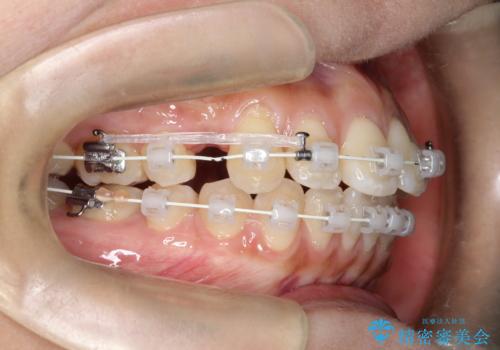

- 矯正装置

- 審美装置

- 前歯の凸凹を主訴に来院されました。

予想治療期間2年でしたが、実際は1年半ほどで終了し満足していただきました。

小臼歯抜歯(上顎4番)して矯正治療を行なったことで、口元もスッキリしました。